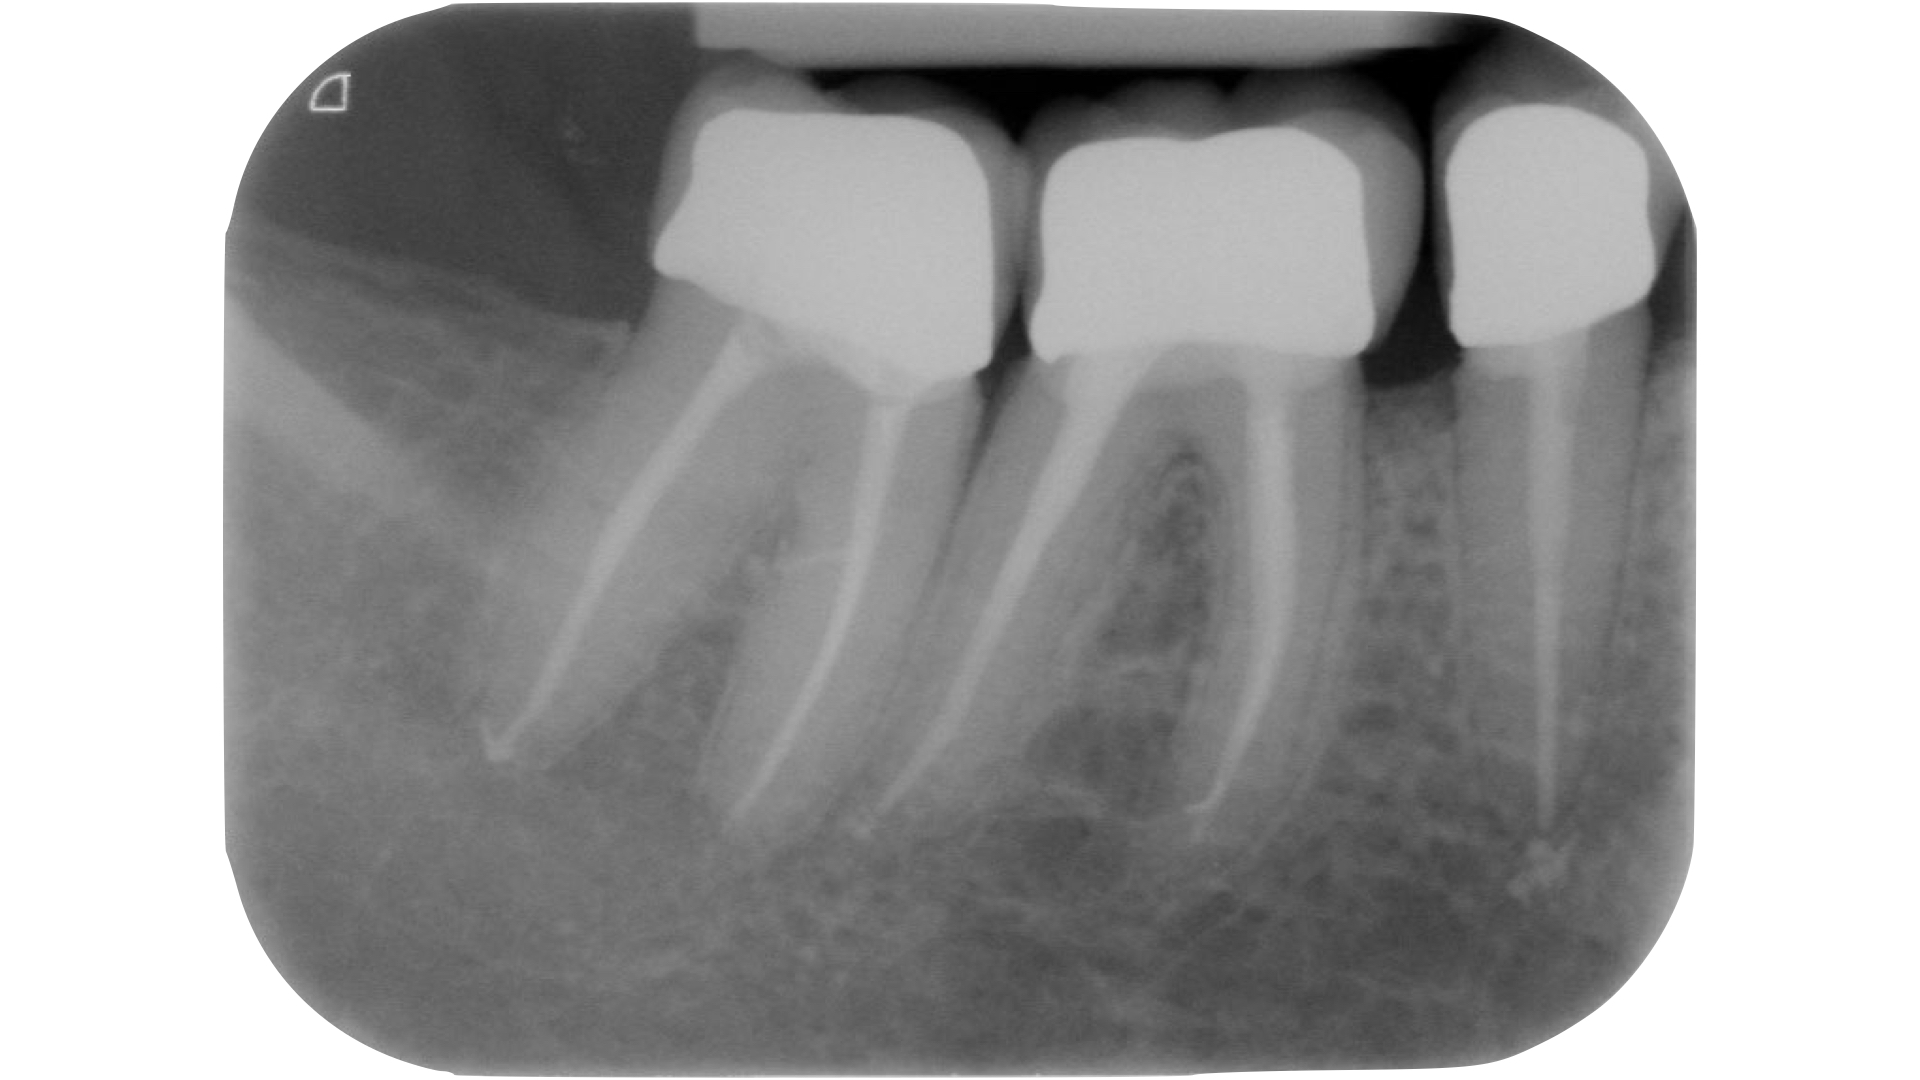

Devono essere valutate con molta attenzione la posizione dell’elemento in arcata e la sua inclinazione (Figure 6-7), l’entità e la posizione del processo carioso se presente, gli eventuali restauri posizionati sul dente e i rapporti con il parodonto: tutte queste considerazioni permetteranno al clinico di capire innanzitutto la mantenibilità e la possibilità di isolare mediante diga di gomma il dente. L’interpretazione degli esami radiografici consentirà inoltre di valutare alcuni parametri preoperatori di notevole importanza:

- qualità dei restauri posizionati sull’elemento dentale ed eventuali infiltrazioni secondarie;

- presenza di radiotrasparenze periradicolari o periapicali;

- difetti ossei di origine parodontale;

- aspetto della camera pulpare e del sistema canalare;

- anatomia radicolare e canalare;

- presenza di pregresse terapie canalari e valutazione della qualità delle stesse;

- presenza o sospetto di riassorbimenti interni o esterni;

- presenza o sospetto di perforazioni e fratture.

Un’attenta analisi di questi dati clinici e radiografici consentirà al clinico di ridurre notevolmente il rischio di errori grossolani in questa delicata fase del trattamento.